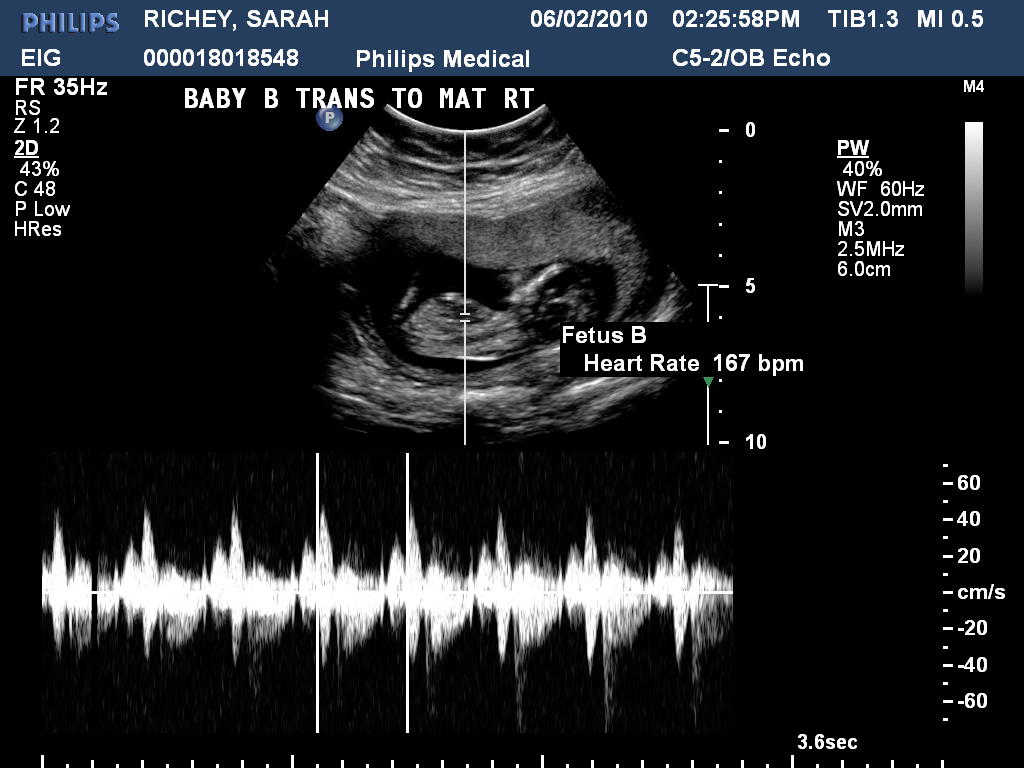

From sjrichey.blogspot.com

The Life of a Fireman's Wife Ultrasound at Winnie Palmer What Does Fhr Mean On An Ultrasound Frequency and intensity of uterine contraction. fetal heart rate monitoring. the current international guidelines of the fédération internationale de gynécologie et d’obstétrique (figo). a normal fetal heart rate (fhr) usually ranges from 120 to 160 beats per minute (bpm) in the in utero period. periodic or episodic decelerations. Changes or trends of fhr patterns over time.. What Does Fhr Mean On An Ultrasound.